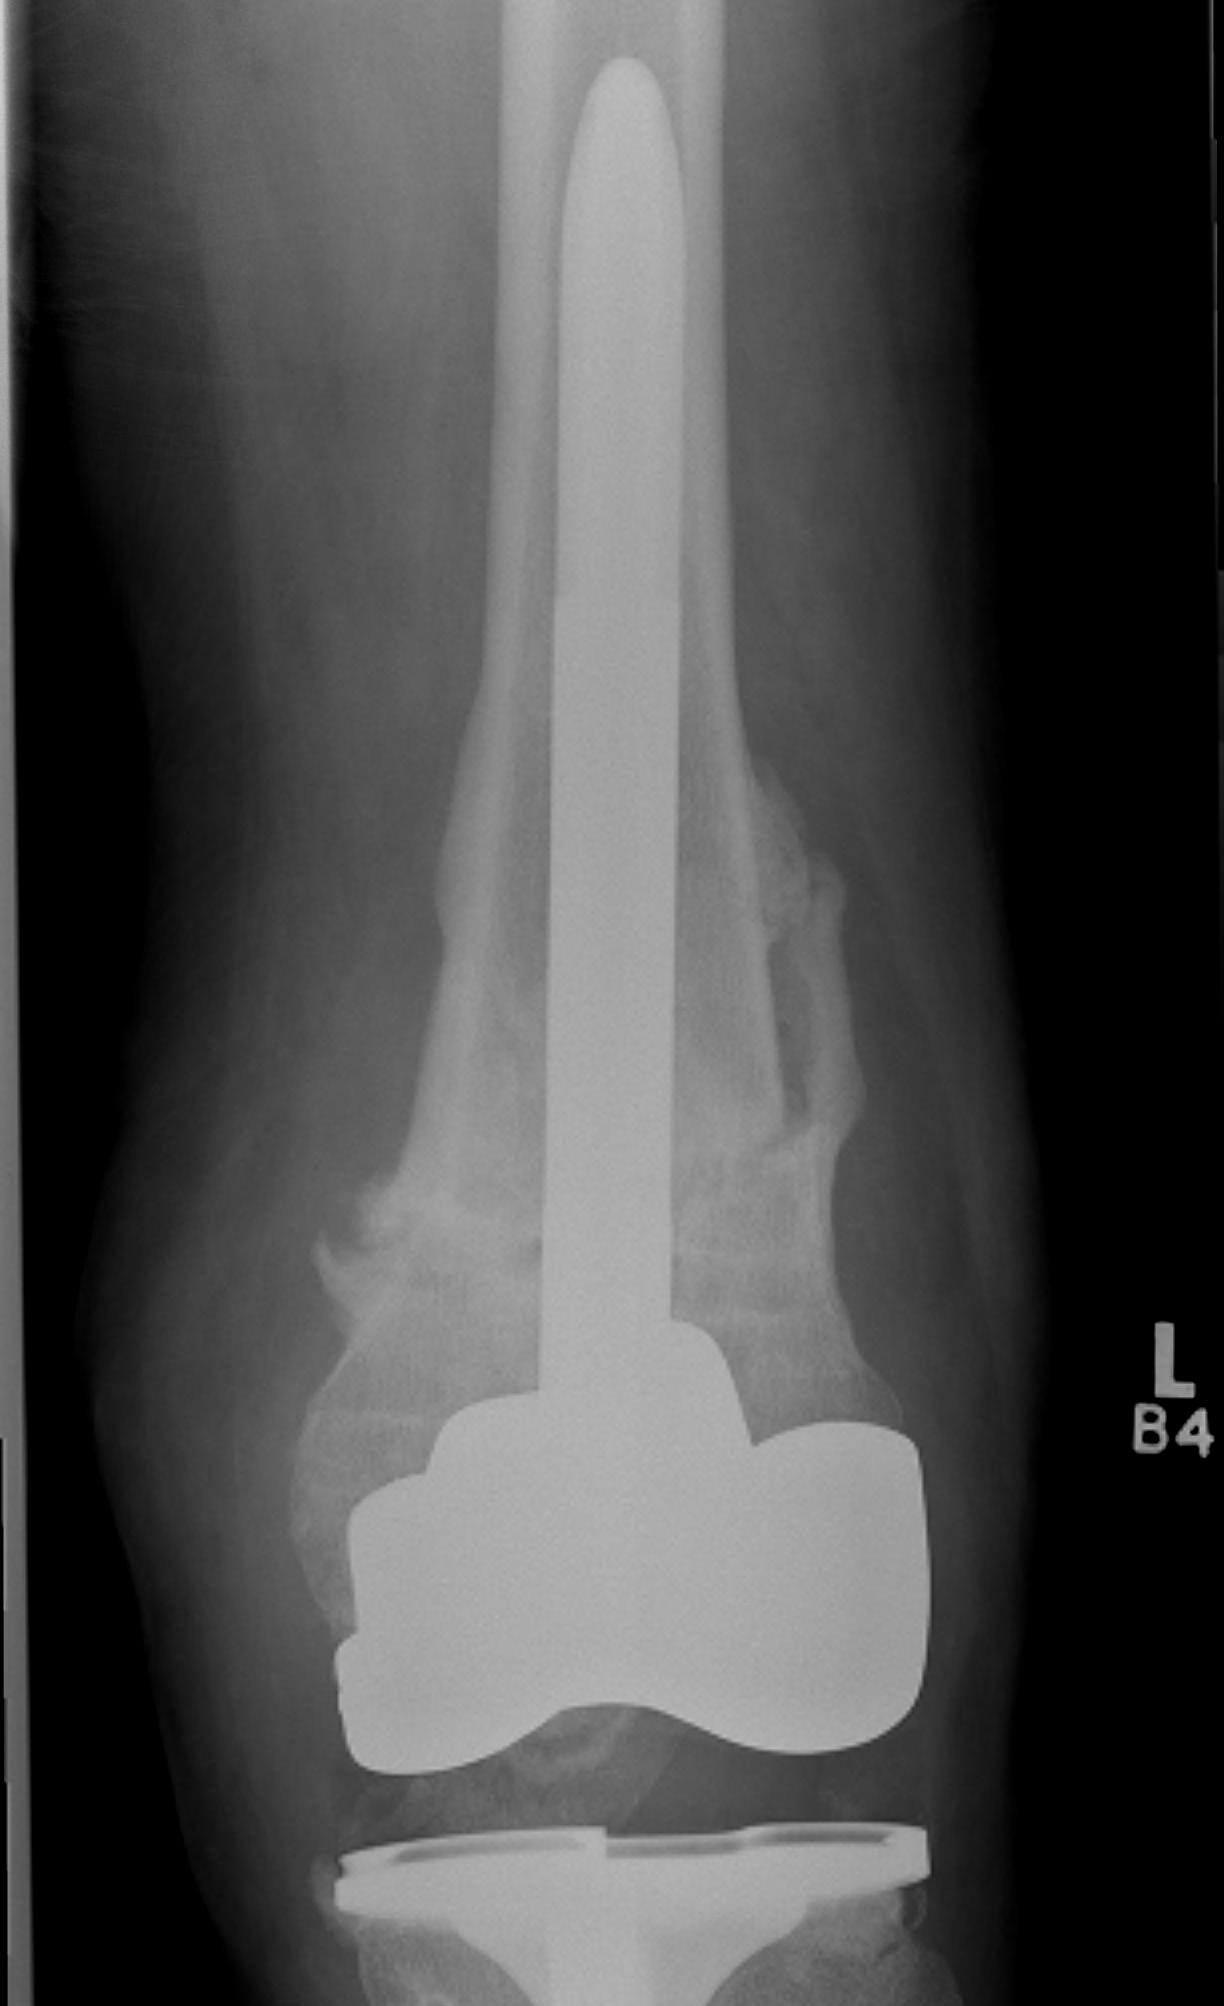

Distal Femoral Replacement

Indications

Elderly osteoporotic patient

Unreconstructable distal femur

Multiple co-morbidities

Difficulty non weight bearing

Results

Hart et al. J Arthroplasty 2017

- ORIF v distal femoral replacement in patients > 70 years old

- reoperation rate 10% in both groups

- 20% non union in ORIF

- at one year, 1/4 ORIF patients wheelchair bound, all DFR patients ambulatory

- AOANJRR review of DFR in native knees

- 10% revision rate at 3y

- most commonly loosening > infection